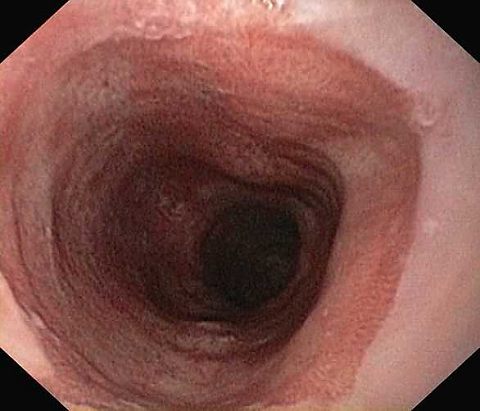

Reflux oesophagitis grade D according to the Los Angeles classification